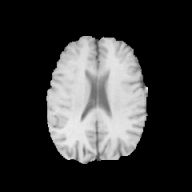

Brats MRI T1 Scans, FLAIR, Tumors. Lastly, we used a dataset of brain MRI scans [28] with two modalities: T1 (naive) and FLAIR (T2 Fluid Attenuated Inversion Recovery) [15]. We adapt the protocol that Cohen et al. [9] used for the Brats2013 datasets [27] to the more recent Brats2018 [3] dataset by varying the percentage of scans with tumors in the target domain. We selected transverse slices from the to range in the caudocranial direction [1] for both T1 and FLAIR scans. Each scan was classified as tumorous if more than of its pixels were labeled as such, and as healthy if it contained no tumor pixels. The training set contains images from each modality, with all source images (T1) being healthy and the target domain (FLAIR) comprising tumorous scans. The test set contains paired scans of healthy brains.

We adapt the protocol of Cohen et al. [9] from the Brats2013 datasets [27] to the more recent, larger, and more diverse Brats2018 dataset [2]. We consider two MRI modalities: native (T1) and Fluid Attenuated Inversion Recovery (FLAIR). We selected transverse slices from the to range in the caudocranial direction [1] for both modalities of scans.

We label each scan as tumorous if more than of its pixels are labelled as such, and as healthy if it contains no tumor pixels. We only use high-grade gliomas (HGG) instead of low-grade gliomas (LGG) as the are more easily observable [24]. In total, we obtain 5035 pathological pairs and 1135 healthy pairs. The train set is composed of a source domain of T1 images of healthy brains, while the target domain set is composed of FLAIR scans of which (60%) are tumorous and healthy. The test set is composed of aligned scans of healthy brains in both modalities.